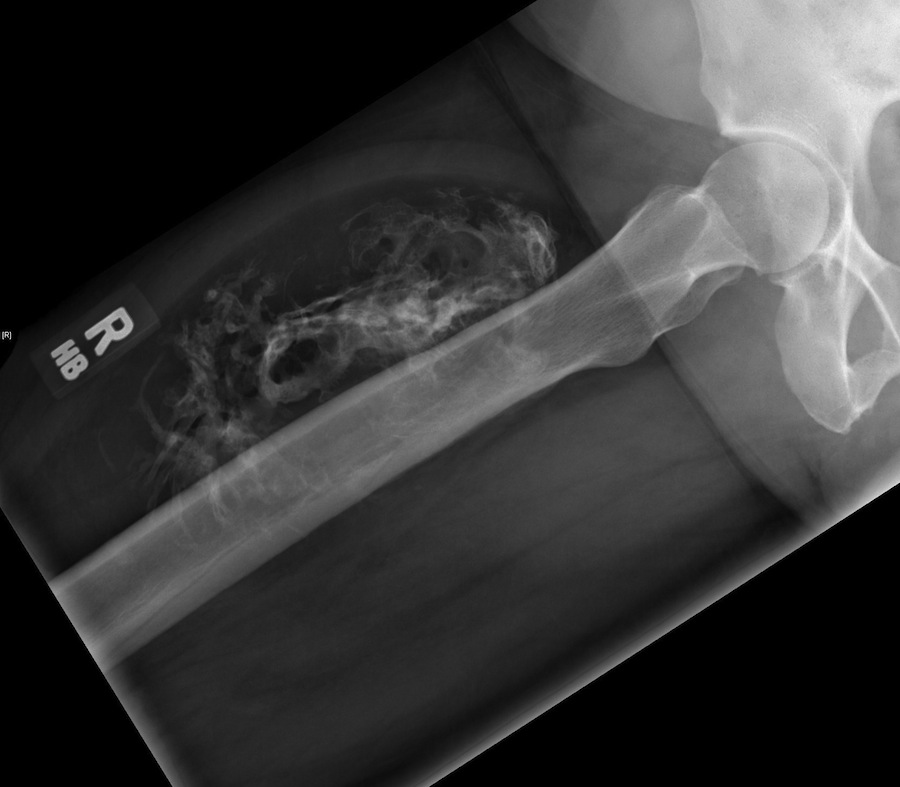

Figure 1 for case Intramuscular lipoma ( RID4350 )

Figure 1

Pathology: Intramuscular lipoma with calcifications.

Intramuscular lipoma ( RID4350 )